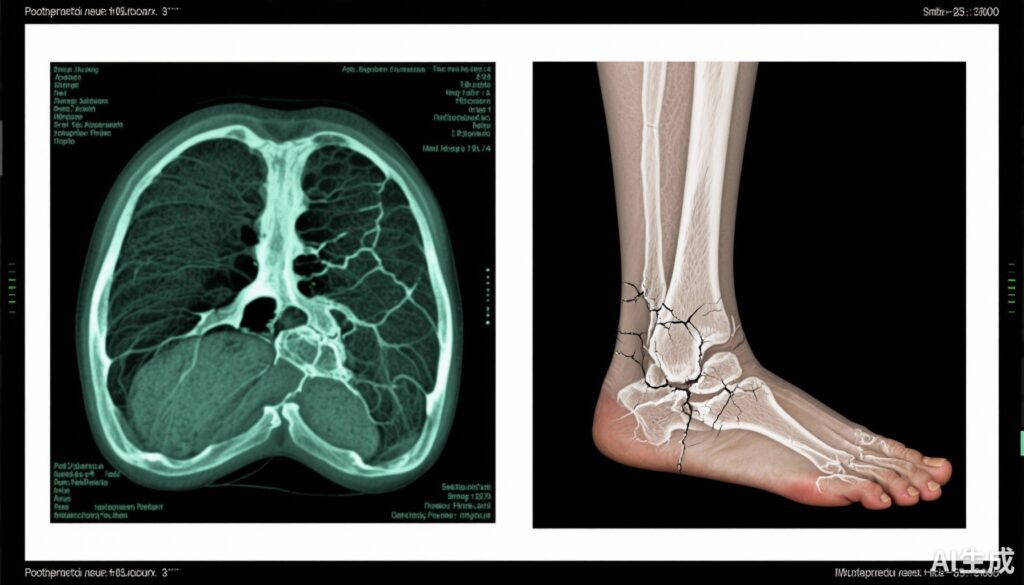

Các phương pháp hình ảnh: Chẩn đoán ban đầu chủ yếu dựa vào X-quang phẳng (93%), nhưng hình ảnh nâng cao mang lại độ nhạy và độ đặc hiệu cao hơn. MRI được thực hiện trong 84% trường hợp, phát hiện các tổn thương căng thẳng xương sớm và định vị chính xác vị trí gãy xương. Chụp hình xương được sử dụng trong 46%, hỗ trợ hoạt động chuyển hóa tại vị trí gãy xương. PET scan ít được sử dụng nhưng có thể mang lại giá trị chẩn đoán bổ sung.

Lâm sàng, phân biệt bệnh xương do methotrexate gây ra từ các gãy xương loãng xương thông thường là điều cần thiết và thách thức. Nghiên cứu ủng hộ việc sử dụng sớm các phương pháp hình ảnh nhạy cảm như MRI. Chụp hình xương đóng vai trò bổ sung quý giá, đặc biệt khi MRI bị chống chỉ định hoặc không sẵn có. Điều trị phải bao gồm việc ngừng sử dụng methotrexate bất cứ khi nào xác nhận bệnh xương do methotrexate gây ra, đồng thời cân nhắc nguy cơ bùng phát viêm khớp.